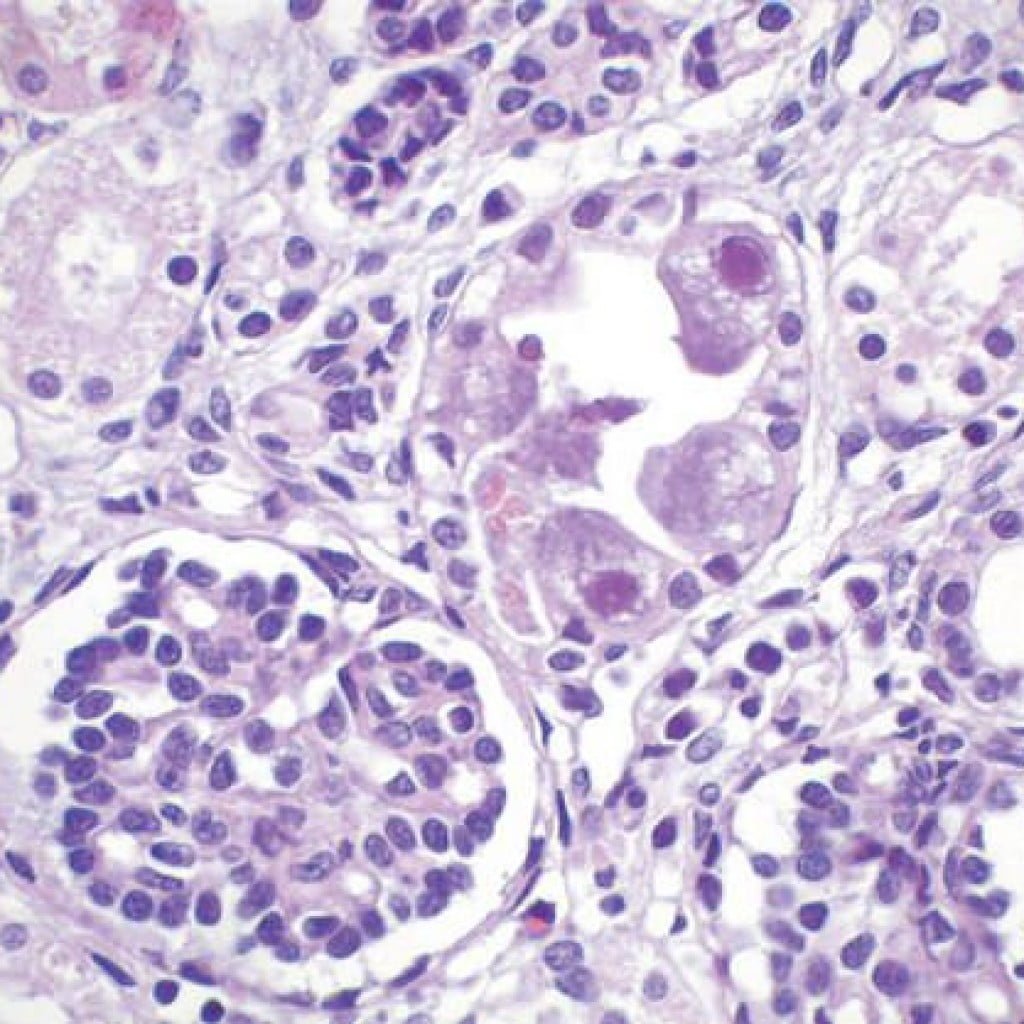

El citomegalovirus pertenece a la familia de los herpesvirus, que incluye el virus de herpes simple, virus de Epstein-Barr y la varicela zóster. Esta familia de virus se caracteriza por su capacidad para producir infecciones latentes y persistentes que puede pasar desapercibidas. Se convierte en patógena especialmente en pacientes cuyos sistemas inmunológicos son débiles: los tratados con inmunosupresores, los afectados por el SIDA y el feto materno. La infección por citomegalovirus en las mujeres embarazadas puede causar daños en el feto.